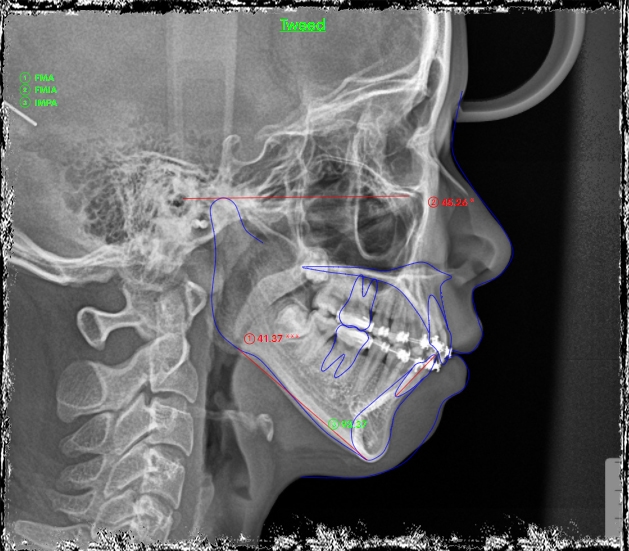

Đánh giá: một trường hợp khe thưa răng cửa giữa hàm trên rất hay gặp trên lâm sàng, nếu không đánh giá đúng tính hình có thể rất dễ bị tái phát do vấn đề khớp cắn, khi đong khe thưa không căn chuẩn thì đường giữa hai răng cửa hàm trên sẽ lệch so với đường giữa mặt (lệch đường giữa hàm trên) và đường giữa hàm dưới có thể không thẳng đường giữa hàm trên.

Phương án: đóng khe thư nhóm răng cửa trước, đánh giá cẩn thận khi đóng khe thưa răng cửa giữa hàm trên và hàm dưới kĩ lưỡng, đưa đường giữa về vị trí chuẩn, sau đó mới đóng hết khoảng và tinh chỉnh khớp cắn.

Kết quả: đường giữa đẹp, khớp cắn ổn sau 1 năm điều trị. Tuy nhiên, BN đeo niền lâu & yếu tố tuổi dạy thì làm tình trạng việm lợi- phì đại lợi tồn tại. BN được tháo mắc cài, hướng dẫn CSRM kĩ lưỡng kèm mát xa lợi, đeo hàm duy trì máng trong. Kết qảu tái khám rất ổn sau 6 tháng.